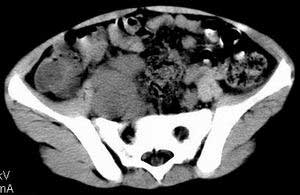

| 患者,男,9岁,因右下腹包块入院,血象不高,不规则发热,常超40度。 平扫: ![]() ![]() ![]() ![]() ![]() ![]() ![]() ![]() ![]() ![]() ![]() ![]() ![]() ![]() ![]() ![]() ![]() ![]() 增强: ![]() ![]() ![]() ![]() ![]() ![]() ![]() ![]() ![]() ![]() ![]() ![]() ![]() ![]() jiajie发言:骶椎右前区不规则软组织肿块,边缘光整,密度均匀,增强后均匀强化,右腹股沟区可见肿大淋巴结,临床有时发热,考虑淋巴瘤,儿童盆腔肿瘤应与神经母细胞瘤和横纹肌肉瘤鉴别。 longzhanghui发言:印象:盆腔右后壁不规则软组织肿块,并向前延伸.似为多个肿块融合,呈中等强化.初步考虑淋巴瘤. 听蝉观竹发言:右侧髂内、外组淋巴结肿大,从其形态和融合的情况看,同意大家意见-----考虑恶性病变,但是9岁男孩还要注意检查睾丸情况,有无隐睾? 常常类似情况是隐睾发生精原细胞瘤淋巴结转移,这个病例也要注意这一点!!! 广东凌发言:大家好,在这里我想说一下个人观点,我建议上传图片的同志能否辛苦一点就是把病史和图片都上传完整一点,比如这个病人的腹膜窗,并且这个病人的肠道的准备也是不怎么好,就从现有的质料看:病灶属于淋巴结肿大当无大的争议,有融合趋势,其内无坏死,边缘强化为主,故考虑:淋巴瘤!建议用腹膜窗看一下和肠道的关系! 阿圣发言:病灶属于淋巴结肿大当无大的争议,有融合趋势,其内无坏死,边缘强化为主,故考虑:淋巴瘤 结果是:淋巴瘤 病例来源:ct762。由宁静致远发布: http://www.radinet.com.cn/forum_view.asp?forum_id=4&view_id=2182 |